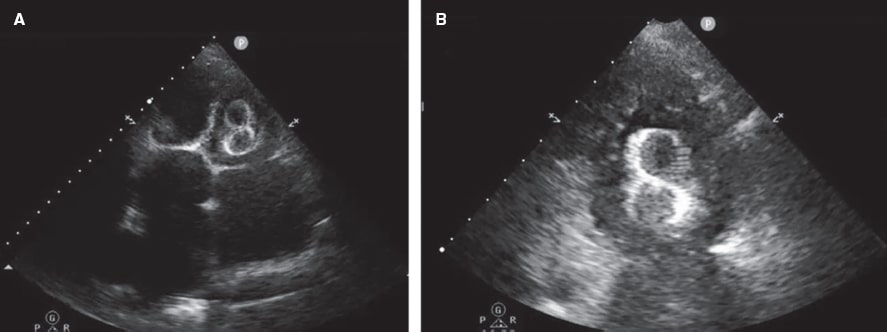

Figure 5 and figure 6 illustrate examples of left atrial appendage device embolization.

Figure 6. Transthoracic echocardiogram (TTE) performed 24 hours after implantation of a 38-mm LAmbre device. A: migration to the left ventricle (LV), with entrapment in the mitral subvalvular apparatus. B: magnified image.